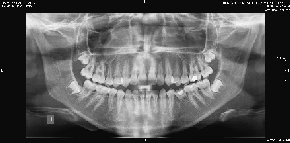

Algunos ejemplos de imágenes digitales

Pulse en las imágenes para ver la ampliación

dientes